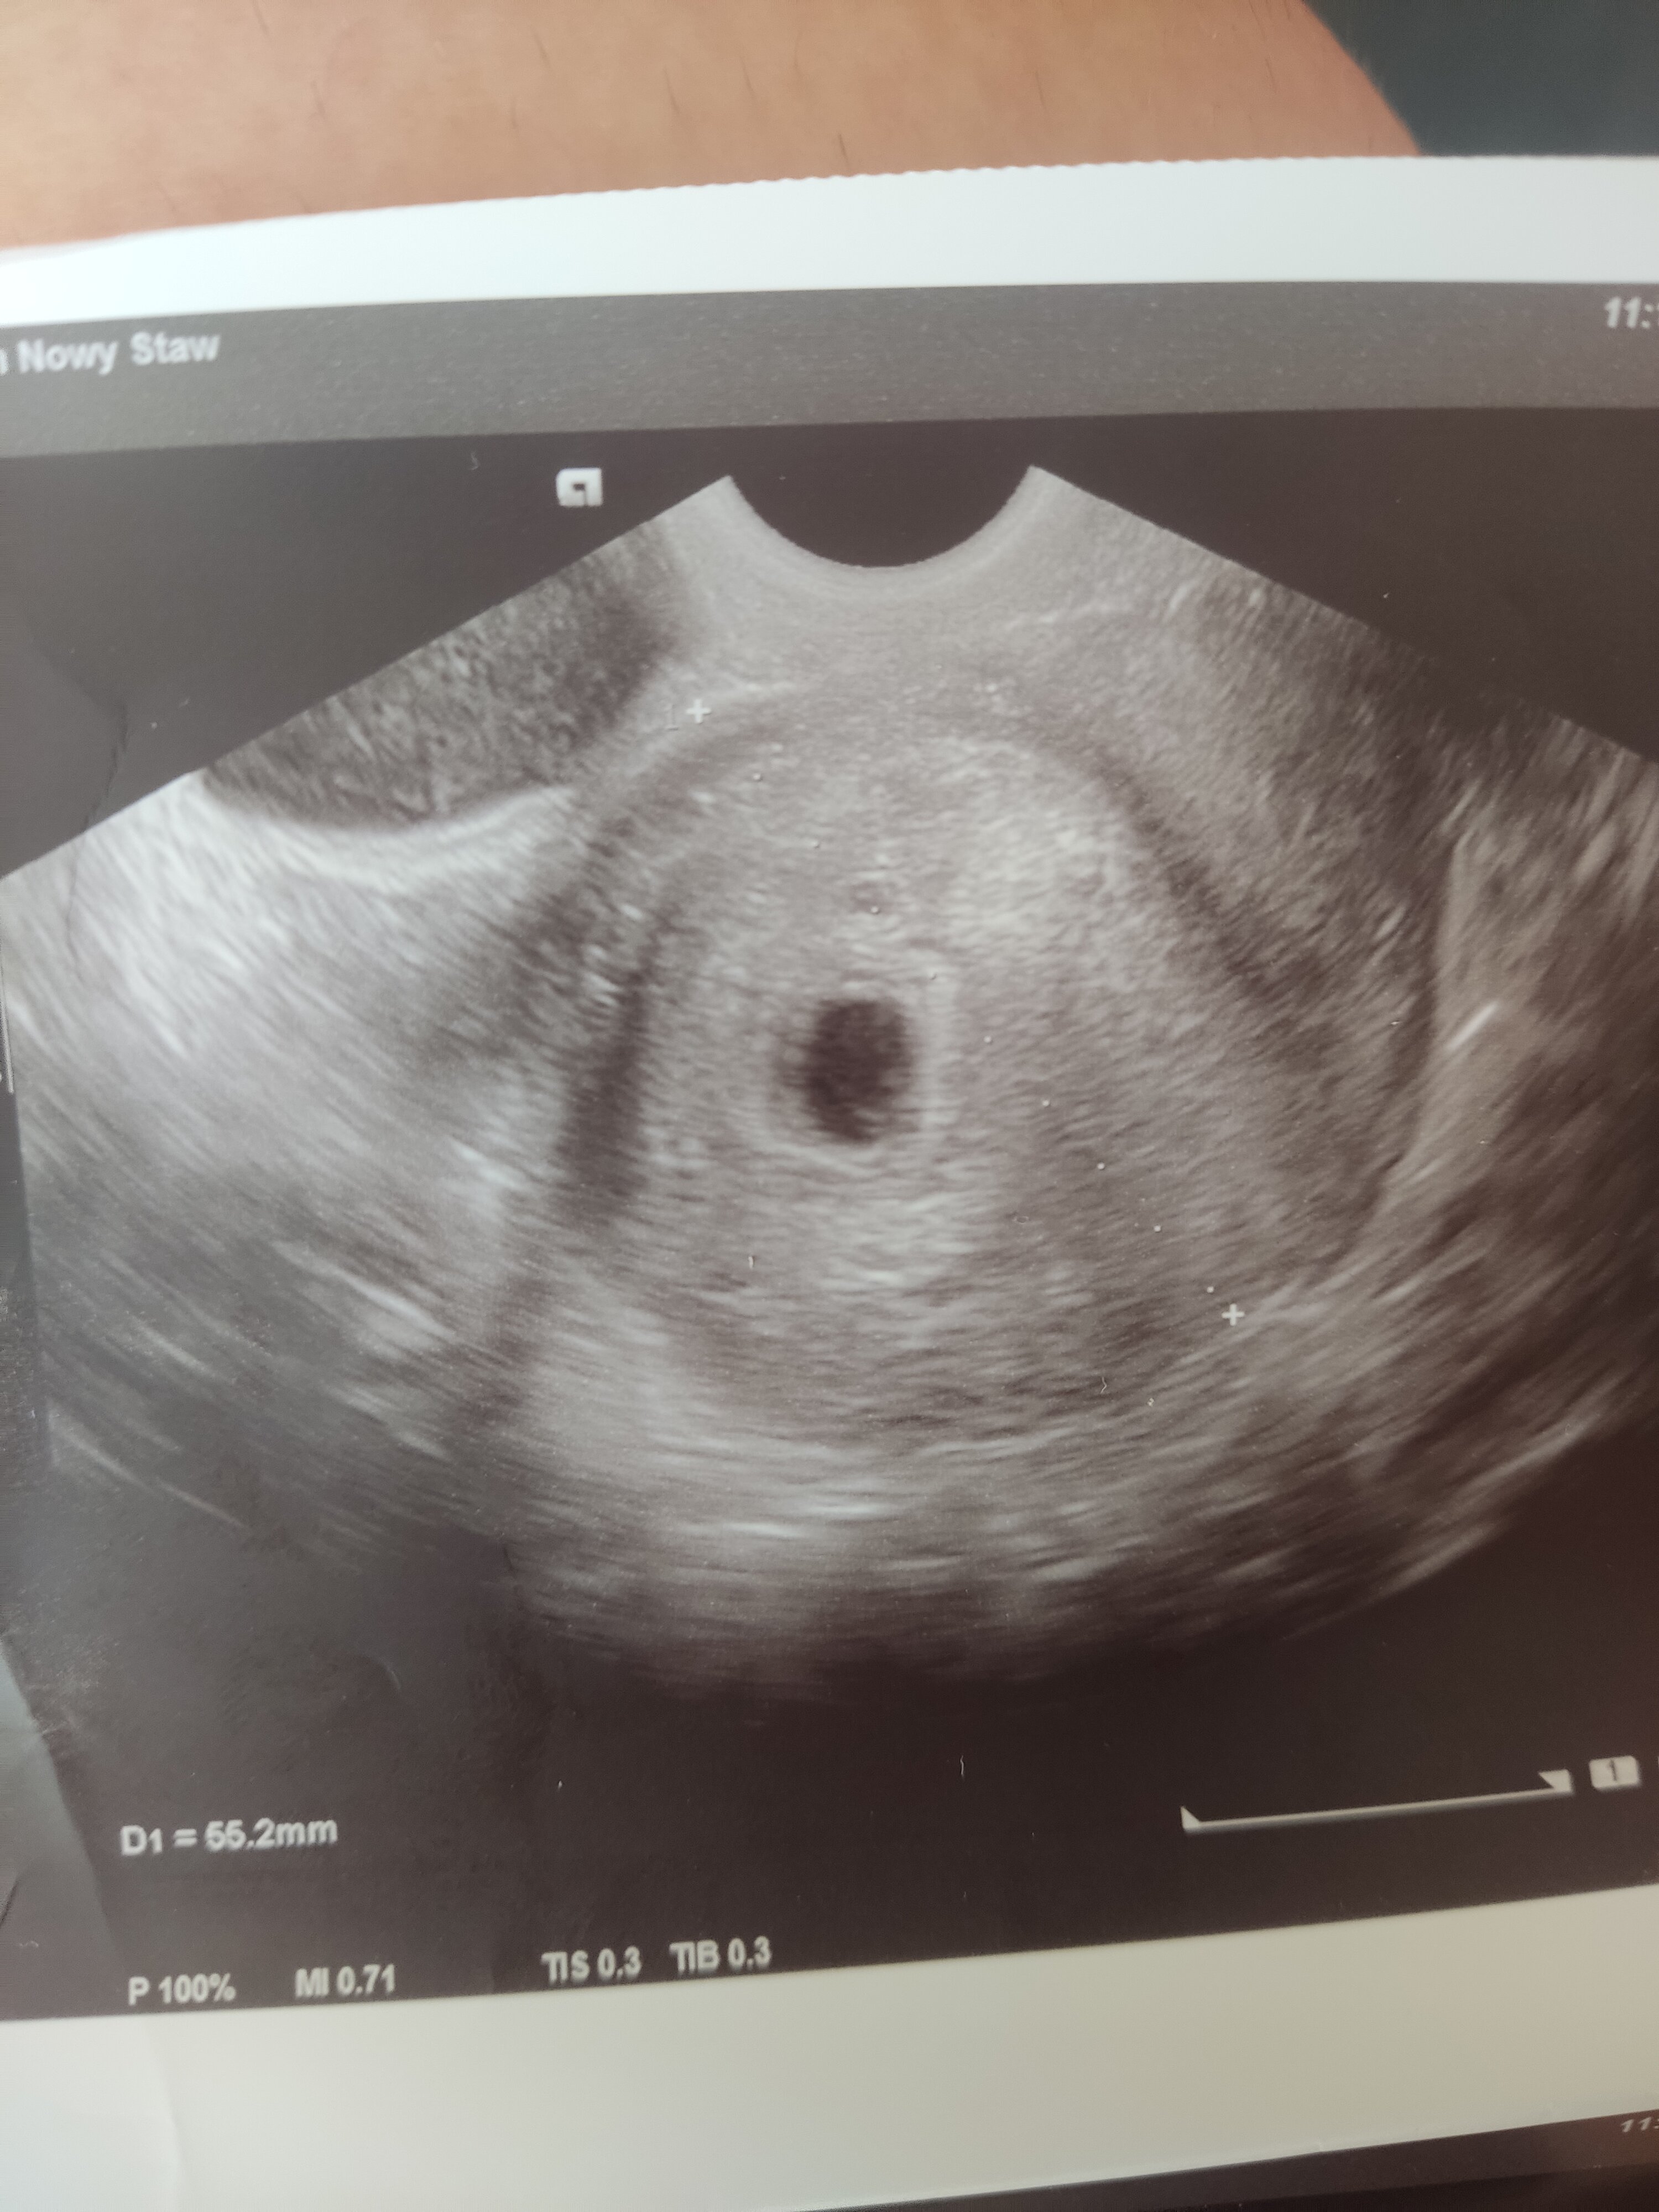

Dzisiaj pierwsze badanie u ginekologa, z ostatniej miesiączki wychodzi 7+5 natomiast z usg młodsza. Pęcherzyk jest wielkości 15,5mm co wdg internetu wskazuję na 6-7 tydzień ale ginekolog stwierdził że to 5tc+0 i mam przyjść za tydzień. Powiedział "spodziewałam się dużo starszej bo dacie ostatniej miesiączki ale przyjdź za tydzień, powinno być serce jeśli się rozwija". Straciłam nadzieję, bo okres miałam 8 kwietnia a 4 maja test wyszedł mi pozytywny, gdyby ciąża była tak młoda jak on mówi to raczej niemożliwe żeby wtedy już była druga kreska na teście. Raczej obstawiam że ciąża się nie rozwija chociaż od tygodnia moje objawy się nasilają. Co myślicie? Widzicie coś na tych zdjęciach? Niestety opisu nie dostałam, bety chyba nie ma sensu robić bo nie robiłam jej ani razu więc chyba lepiej czekać na usg za tydzień :/

Pęcherzyk wygląda na pusty no, ale to tylko zdjęcie nie wiem czy lekarz widział pęcherzyk żółtkowy. Tak czy tak trzeba sprawdzić za kilka dni, nic innego się tu nie wymyśli